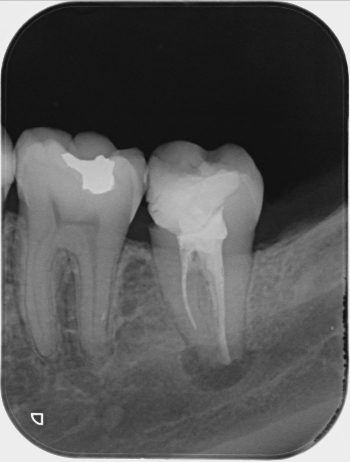

Fotos de casos clínicos